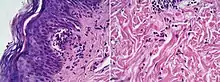

Spongiotic dermatitis

It is characterized by epithelial intercellular edema.[2]

| Generally/Not otherwise specified[notes 2] | Typical findings:[2]

Typical findings:[2]

Typical findings:[2]

PAS stain is essential to exclude fungal infection.[2] |

Subacute Subacute |

| Allergic/contact dermatitis or atopic dermatitis | As above. Eosinophils may be present in the dermis and epidermis (eosinophilic spongiosis).[2] |  Allergic dermatitis Allergic dermatitis |

In addition to above, an unspecific spongiotic dermatitis can be consistent with nummular dermatitis, dyshidrotic dermatitis, Id reaction, dermatophytosis, miliaria, Gianotti-Crosti syndrome and pityriasis rosea.[2][notes 2]